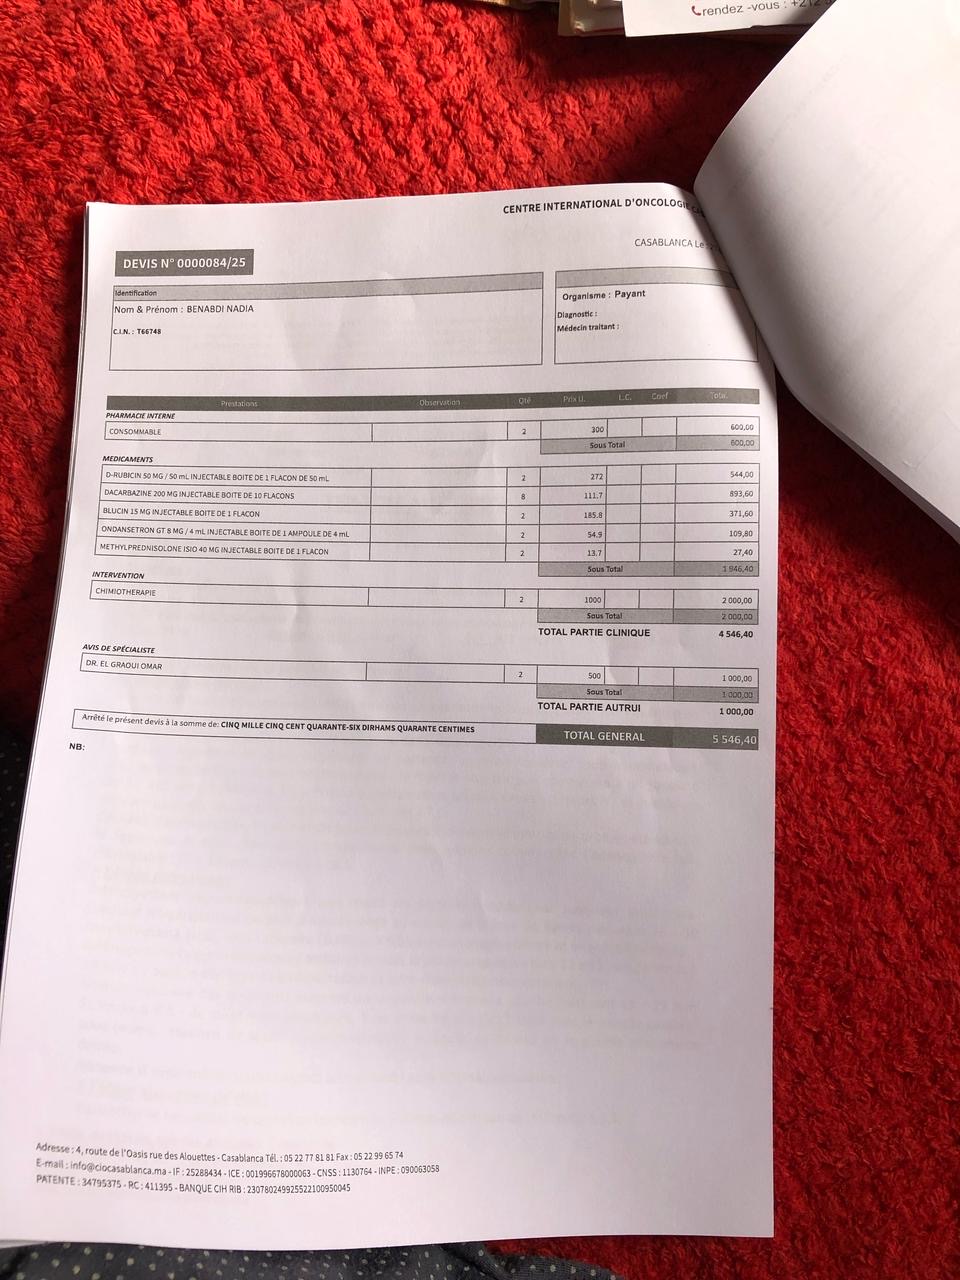

Je m’appelle Hajar, je vis et travaille à Montréal, mais ma maman, qui ne vit pas avec moi, traverse une période très difficile. Elle a été diagnostiquée avec un lymphome de Hodgkin de stade 3, une maladie grave qui nécessite un traitement coûteux : médicaments, examens et séances de thérapie. Malheureusement, ces frais sont un fardeau trop lourd pour notre famille.

Je veux être là pour elle et l’aider à recevoir les soins médicaux dont elle a besoin, mais seule, je ne peux pas tout assumer. C’est pourquoi je fais appel à votre générosité.

My name is Hajar. I live and work in Montreal, but my mother, who doesn’t live with me, is going through a very difficult time. She has been diagnosed with stage 3 Hodgkin’s lymphoma, a serious illness that requires expensive treatment, including medication, tests, and therapy sessions. Unfortunately, these costs are an overwhelming burden for our family.

I want to be there for her and help her get the medical care she needs, but I can’t do it alone. That’s why I’m reaching out for your generosity.